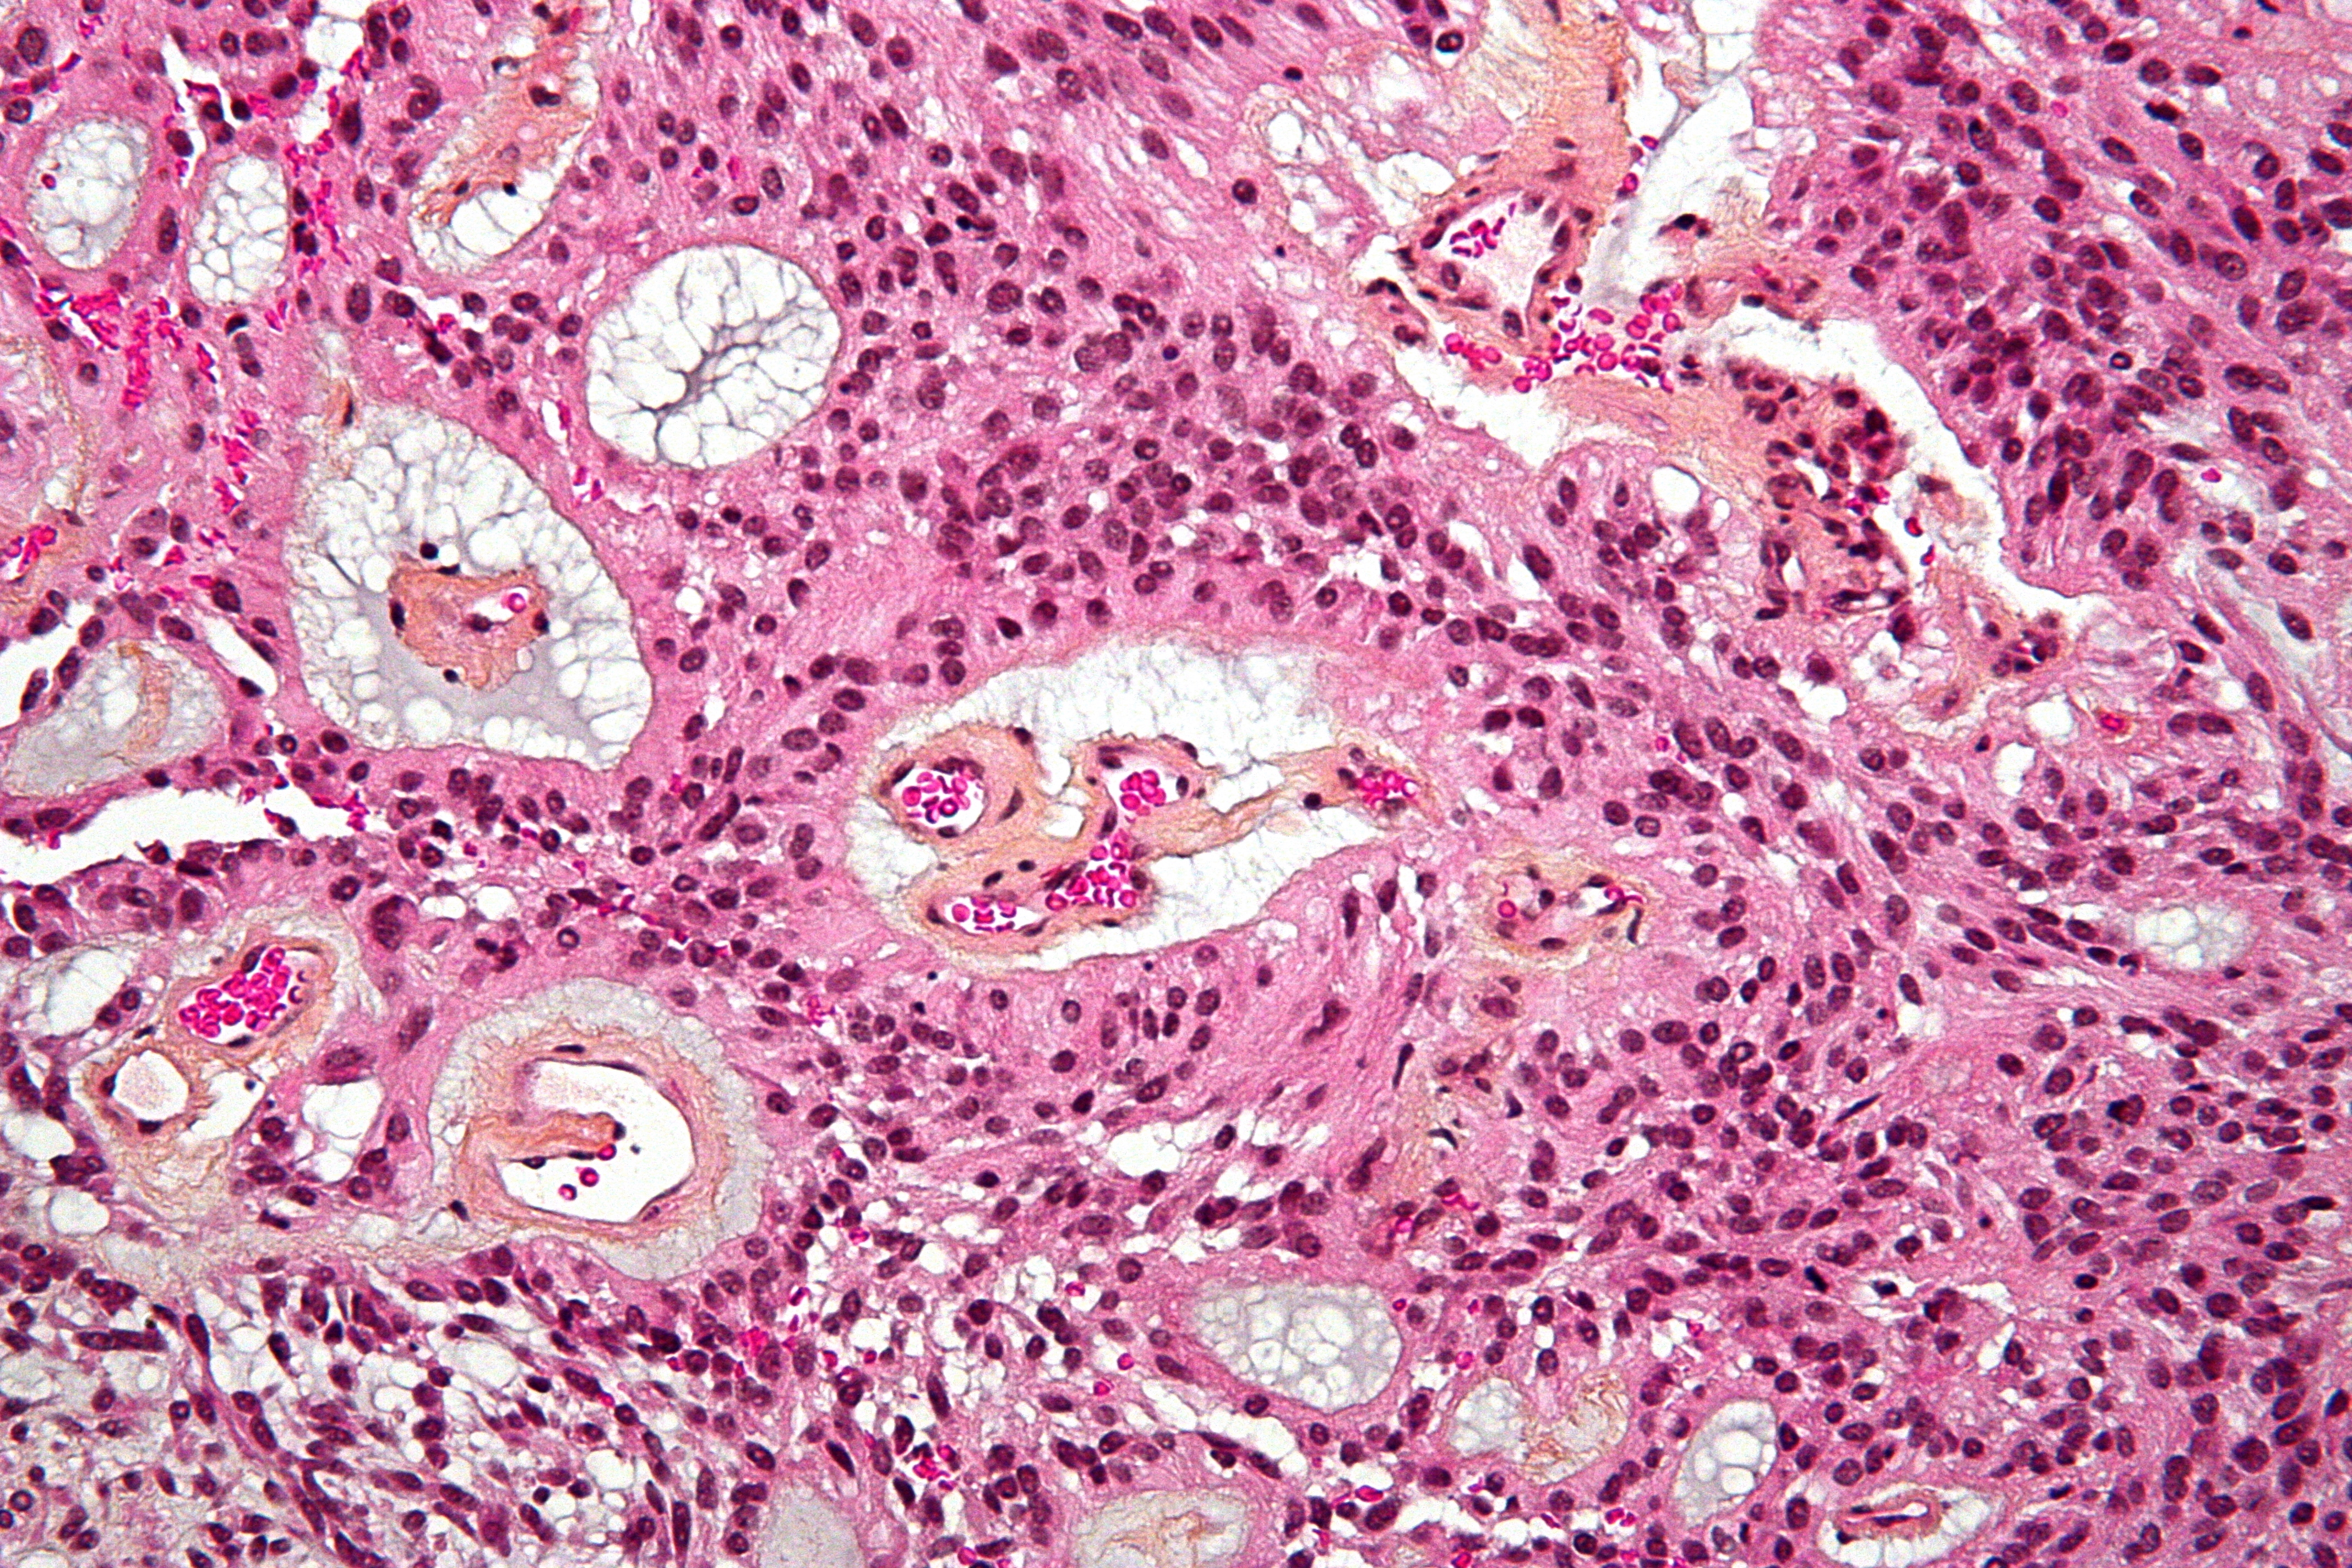

Ependymoma accounts for less than 2% of all adult brain tumors. Rosette formation is a hallmark of ependymoma with increased cellularity, cytological atypia and microvascular proliferation which suggests ependymoma.

WHO Grade III

• anaplastic ependymoma

• increased cellularity and increased mitotic activity

• mircorvascular proliferation

• necrosis